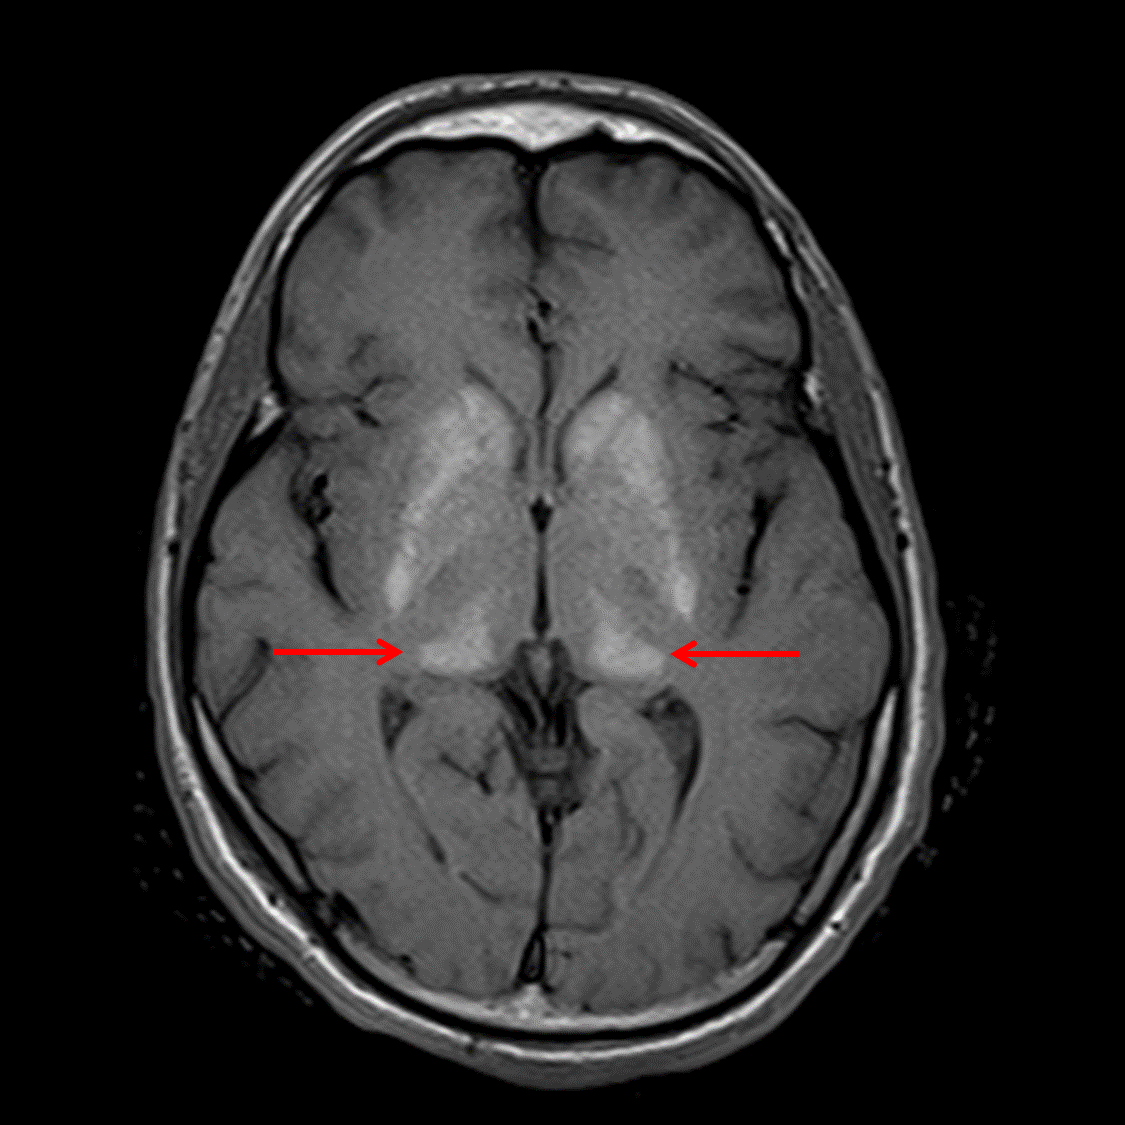

Fabry disease

Symmetric T1 signal hyperintensity involving the bilateral basal ganglia, thalami (especially the pulvinar), and dentate nuclei with corresponding susceptibility artifact, likely relating to mineralization. Additional linear areas of susceptibility artifact involving the bilateral cerebral subcortical and deep white matter, most pronounced in the frontal lobes also likely represent mineralization. Given distribution and patient age, these findings are favored to represent Fabry disease. Disorders of calcium homeostasis including hyper- and hypoparathyroidism are additional diagnostic considerations.

Patchy T2/FLAIR hyperintensities in the bilateral frontal periventricular white matter, which are nonspecific but may relate to chronic small vessel ischemia.